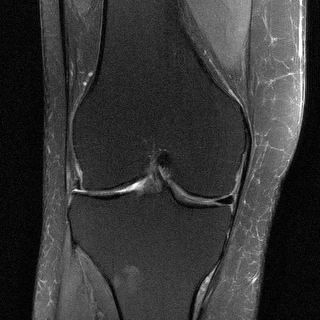

ニューヨーク大学医学部放射線科教授のダニエル・ソディクソン氏によると、MRIスキャンが遅い理由は、放射線科医が読影しやすい鮮明な画像を生成するために必要なデータをすべて取得する必要があるためです。膝のスキャンには15~20分、脳のスキャンには30分、心臓の撮影には1時間かかります。しかし、もしMRI装置の動作速度を上げて、なおかつ実用的な画像を取得できたらどうなるでしょうか?

彼らのやり方はこうです。MRIスキャンをより高速に実行し、その過程で収集する生データの量を減らします。しかし、従来の方法(AIを使わない、実績のある数学的プロセス)で生データを解釈するのではなく、データから画像への変換を人工知能に学習させます。研究者が従来の方法で高速MRIデータを解釈しようとすると、そもそもデータが不足しているため、結果は良くありません。AIを使えば、より良い結果が得られます。

もちろん、通常よりも少ないデータから画像を作成するのはリスクがあるように聞こえます。AIがデータを解釈して見栄えの良い画像を生成したとしても、何か重大なものを見逃していたらどうなるでしょうか?靭帯の小さな裂傷や小さな腫瘍など?ソディクソン氏によると、それが彼らの最大の懸念事項だそうです。「提示している情報が真実であることを確認する必要があります」と彼は言います。「それを検証する方法はたくさんあります。」

AIはまだ、高速スキャンから、低速の通常スキャンから得られる画像と同等の画質の画像を生成できていません。しかし、AIは従来の方法よりも少ないデータから画像を生成する能力を既に向上させています。「これまでのものよりは優れていますが、まだフルスキャンほどの画質ではありません」と彼は言います。